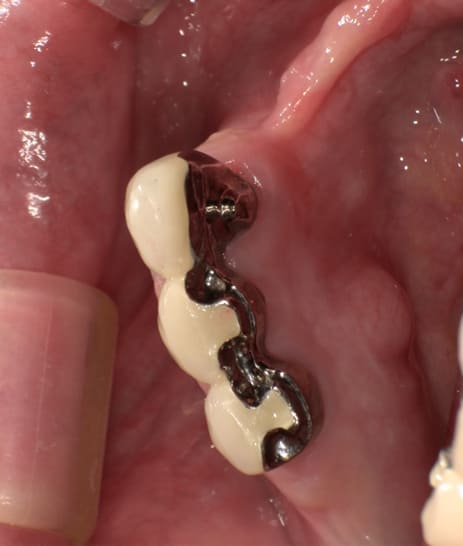

下顎治療前

-

下顎治療後

治療前の入れ歯の奥歯は、治療後の義歯と比較しても分かるように、歯が削れ平らになった状態です。

これにより奥歯のかみ合わせは低くなり、前歯のみが強くあたり、かみ合わせにより上の前歯大きな負担がかかっていたことにより、上の前歯が折れたことが考えられます。